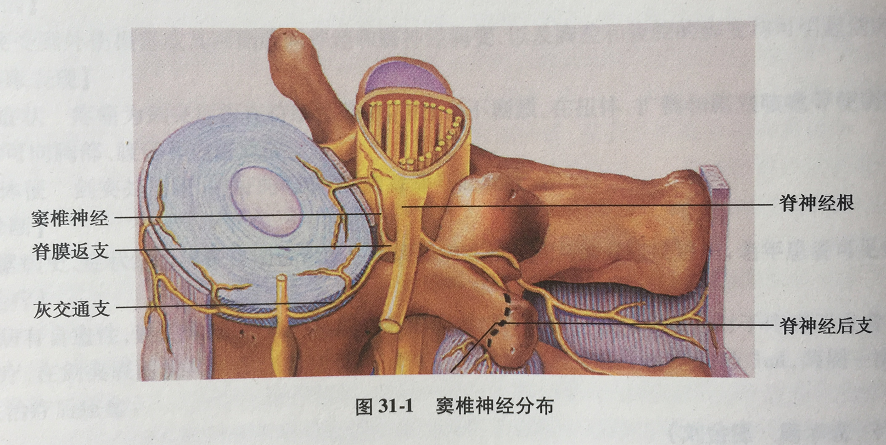

- 纤维环的前、外侧面和前纵韧带由脊神经前支和灰交通支支配,而后面和后纵韧带由窦椎神经支配

2、窦椎神经(lumbarsinuvertebral nerve, LSVN):

- 又称Luschka神经,在脊神经分为前后支之前发出,内含交感神经纤维和来自脊神经节的感觉纤维,经椎间孔返回椎管,分为较大的升支和较小的降支

- 发出的分支分布于其上和下2-3个硬脊膜前部、后纵韧带、纤维环后部外层